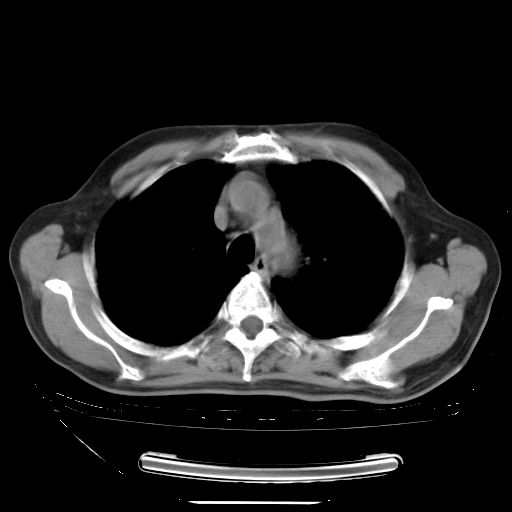

今天复查肺部CT,发现双肺广泛磨玻璃样改变。所以我把3月19日和5月9日相隔50天的肺部CT上传。请大家会诊。

2009年3月19日肺部CT片。

2009年3月19日肺部CT